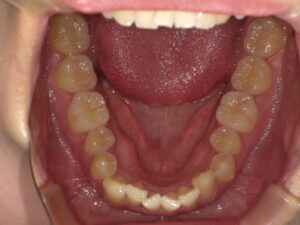

はじめに|「上はキレイなのに…」下の歯だけガタガタな理由とは?

鏡で自分の歯並びを見たとき、「上の歯は整っているのに、下の歯だけガタガタしている…」と気になったことはありませんか?

実はこの「下だけ乱れている」というパターン、矯正相談に訪れる方の中でも非常に多いケースです。